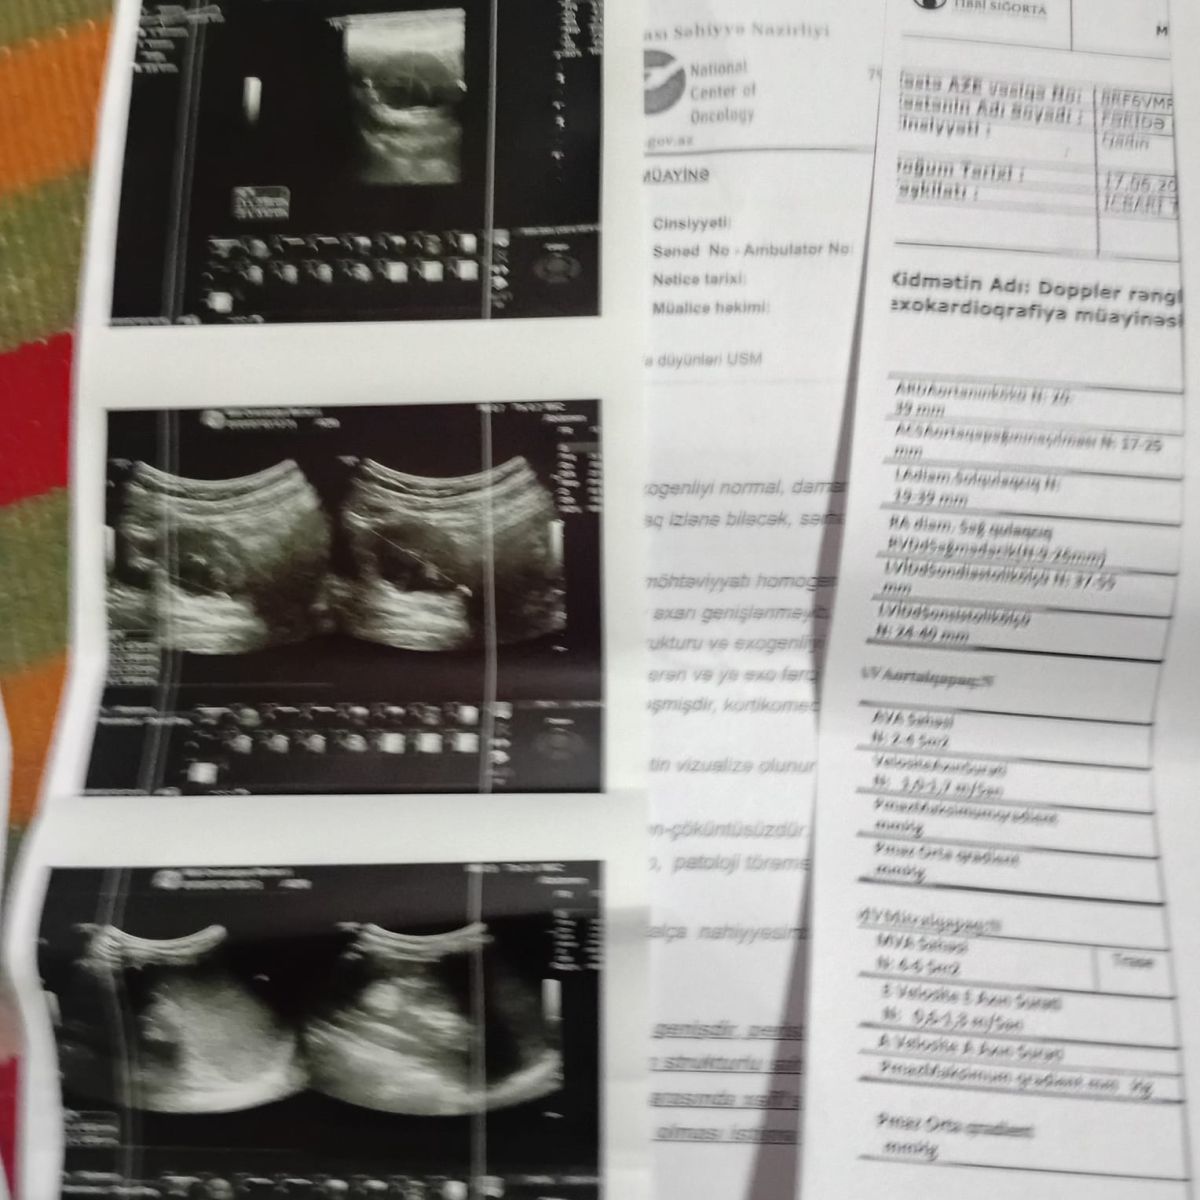

Медицинские справки публикуем ниже.